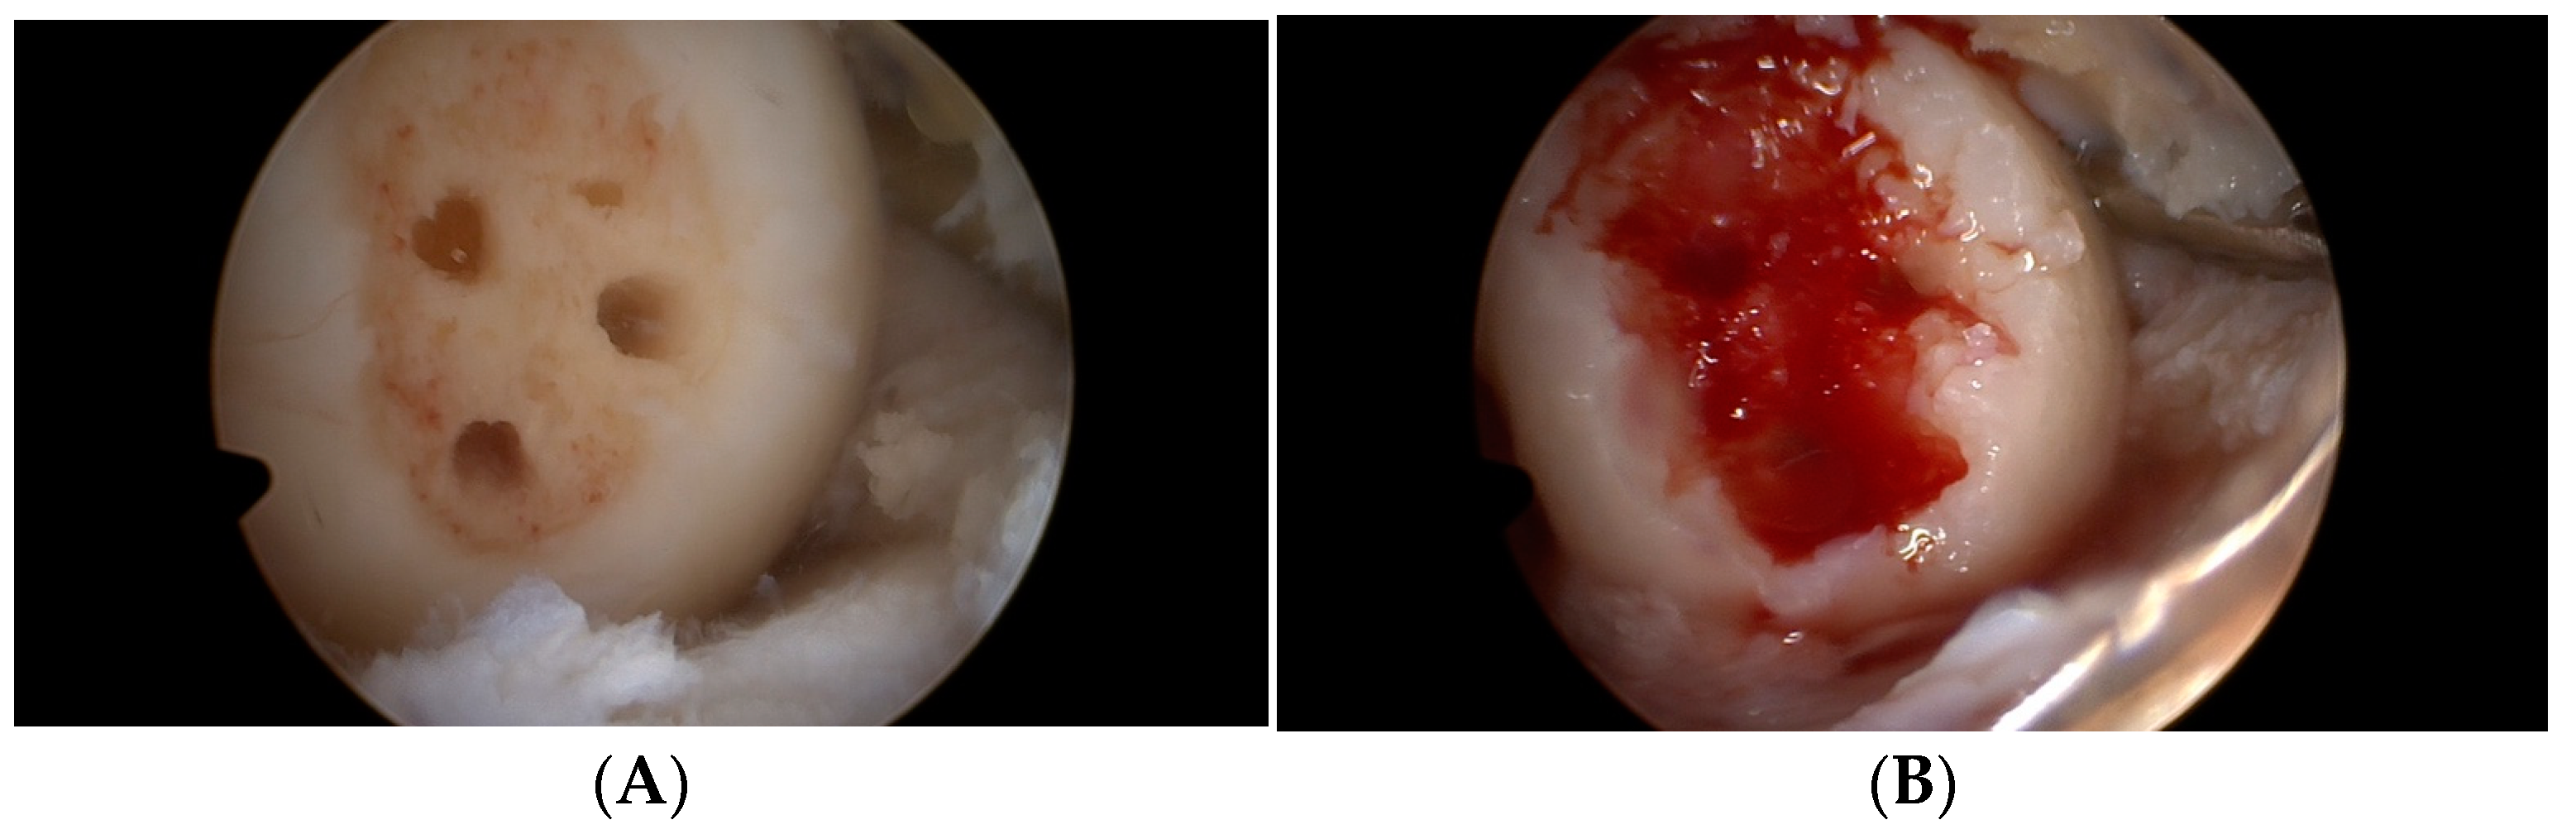

2.2. Operation Procedure